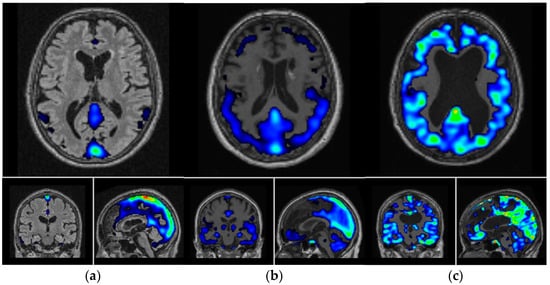

- Shimada, H.; Kitamura, S.; Shinotoh, H.; Endo, H.; Niwa, F.; Hirano, S.; Kimura, Y.; Zhang, M.R.; Kuwabara, S.; Suhara, T.; et al. Association between Abeta and tau accumulations and their influence on clinical features in aging and Alzheimer’s disease spectrum brains: A [11C]PBB3-PET study. Alzheimer’s Dement. 2017, 6, 11–20. [Google Scholar] [CrossRef]

- Chiotis, K.; Stenkrona, P.; Almkvist, O.; Stepanov, V.; Ferreira, D.; Arakawa, R.; Takano, A.; Westman, E.; Varrone, A.; Okamura, N.; et al. Dual tracer tau PET imaging reveals different molecular targets for 11C-THK5351 and 11C-PBB3 in the Alzheimer brain. Eur. J. Nucl. Med. Mol. Imaging 2018, 45, 1605–1617. [Google Scholar] [CrossRef]